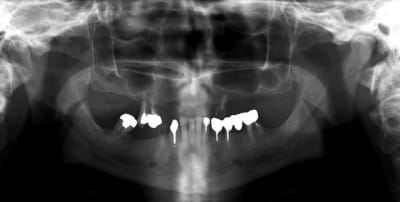

je ne voudrais pas "louper " ce cas, alors quelles idées de traitements auriez vous à me soumettre ?

pas de pb de santé

portefeuille pas extensible...

quand je disais "portefeuille pas extensible", je voulais dire qu'il n'était pas question de proposer un traitement avec 14 implants...

8 devraient suffire ,non?

8 en haut tu veux dire...avec 2 sinus lift...et un grand bridge transvissé de 16 à 26 par exemple???

pour le haut, mais si tu ne fais rien en bas, ça va pas le faire.

quand je dis 8, c'est huit pour le haut et le bas.

bien sure il faut tout revoir, l'occlusion, la DV, la courbe occlusale, la ligne du sourire...

extraction: 14-15-23-44 et 36 (ou amputation, mais à quoi bon ?)

reprendre la courbe occlusal avec des céram sur 43-46-33-34

bridge sur implant sur 44 -46 et 35-36 (ou 35-37?)

complet haut amovible sur deux barres (donc 4 implants en haut) ou sur 4 locators (y en a qui ont déjà fait ?)